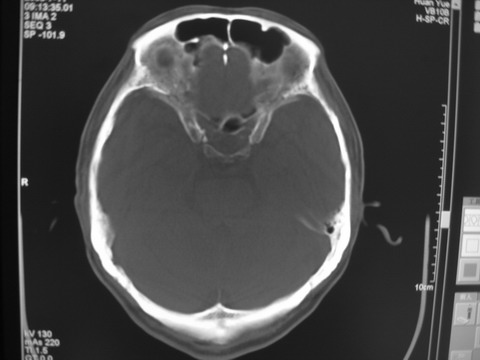

患者 男 69岁 头晕头痛不适

多发病灶,指状水肿,首先诊断转移瘤。

多个结节并周围大面积水肿区,多考虑多发性脑转移瘤

小病灶、大水肿,病灶多发,首先考虑多发转移瘤;建议查原发灶。

额顶叶多发小病灶、大水肿,首先考虑多发转移瘤;建议查原发灶

脑内多发病灶,小病灶,大水肿。

典型转移性肿瘤。

应进一步检查,查找原发病灶。

结果 : 该患者结肠癌病史5年 考虑脑转移